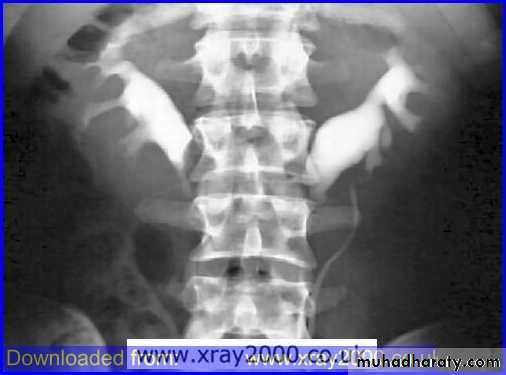

Horse shoe kidney -Kidneys may fail to separate.

-Almost invariably the lower poles remain fused.

-The kidneys axes are more parallel to the spine and malrotated.

-Diagnosis can be made by plain x-ray in some cases.

-US, CT scan and MRI can better demonstrate the anatomy and morphology hence the diagnosis.

-May be an incidental finding.

-PUJ obstruction and calculi formation are common .

IVU shows

1. The kidneys at low position .

2.Close to the spine with long axis parallel to the spine .

3. Malrotation manifested by medially directed calyces.

4- The renal pelvis and ureters are anterior and lateral in position .